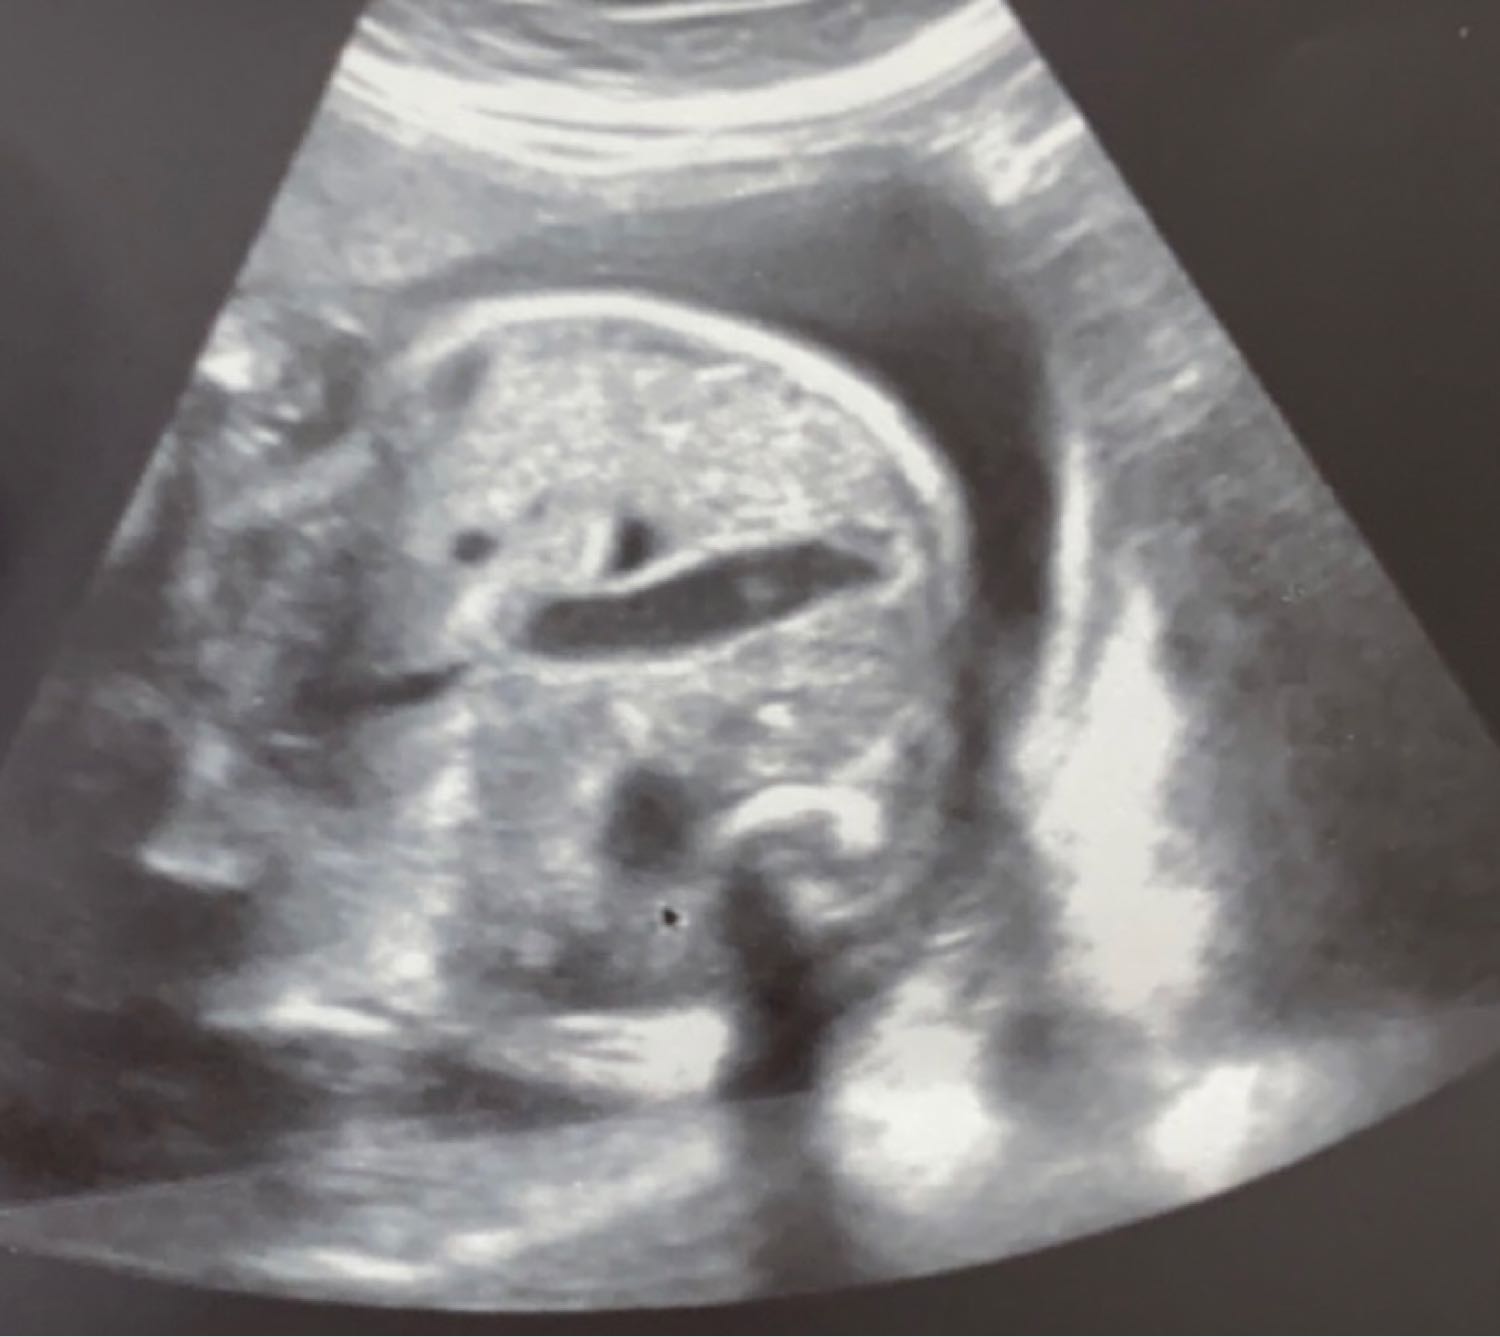

Девочки всем привет! У меня паника, сегодня была на узи. Поставили диагноз у ребенка «Пневматоз кишечника» говорит скапливание газов или жидкость(киста). Сказали что это уже патология, напугали меня. Направили сделать экспертное узи на 32 нед. Я очень много колы пью и до беременности пила и здесь писала насчет этого, говорят из-за этого типа у ребенка это все. Я теперь себя виню. Но с одной стороны, я болела в мае орви, но темп не было, узист говорит может из-за этого. Короче не знаю девочки, прочтете узи, скажете кто что знает? У кого было? Что было в итого? Как ребенок родился? P.S. На фотках то самое расширение

Так у вас в диагнозе пневматоз плаценты , а ни у ребенка газы. Плацента и ребенок это разное.

Тако 💁🏻‍♀️ , Киста плаценты. А у ребенка увидела пневматоз. Возможно это просто воздух или газики, не обязательно сразу ставить такой диагноз. Сходите к другому врачу